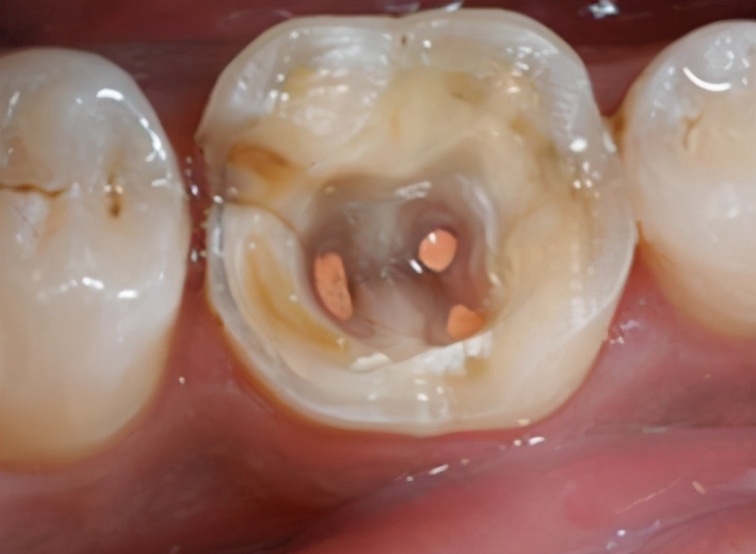

所以对于龋坏的牙齿,一定不能放置不管,龋坏因子无时无刻都在进攻我们的牙齿,唯有及时的治疗才能阻断其再发展!而对于蛀牙的具体治疗方式有补牙、根管治疗等。

究竟哪一种治疗方式适用,需要根据蛀牙的发展程度、是否已经深入到牙齿内部而定。这需要专业医生对牙齿情况进行专业的检查、判断后方可确定治疗方案。所以及时就医,是重中之重!